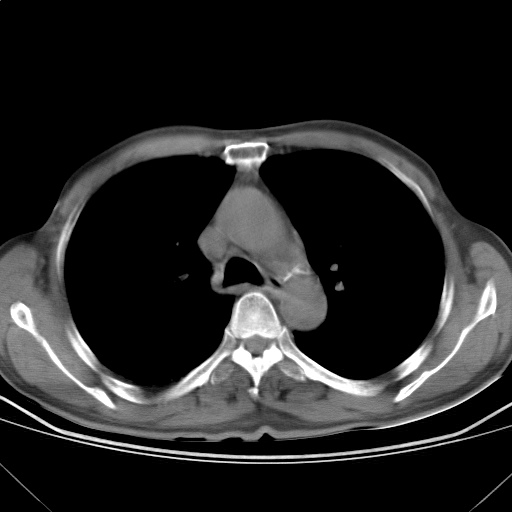

以下是引用随光逐影在2009-5-1 13:53:00的发言:[br]考虑为:1)两肺血行播散型肺结核;2)右肺下叶炎症感染。3)右侧胸膜增厚。